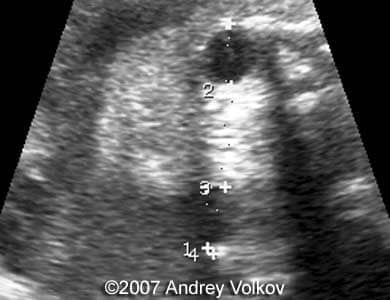

A 26-year old G1P0 from a nonconsanguineous couple (husband 35 years old), with noncontributive history, presented to our unit at 30 weeks of pregnancy. Our ultrasound examination revealed following findings:

• Lobar holoprosencephaly;

Images 1, 2: 30 weeks of pregnancy; Image 1 shows cloverleaf shaped fetal skull. Image 2 shows transverse scan through the fetal skull with lobar holoprosencephaly.